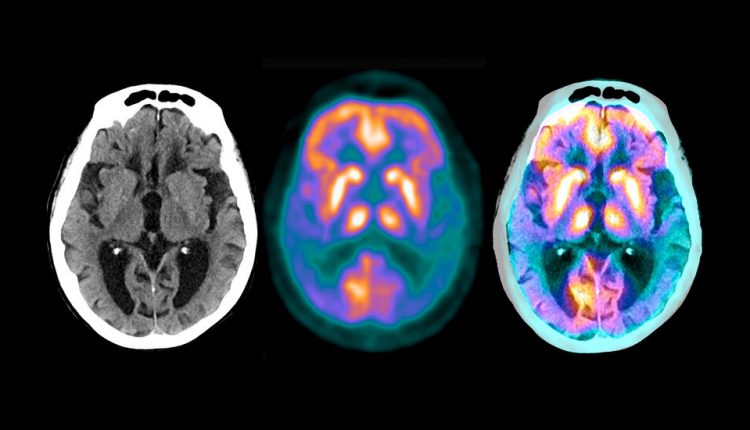

The drug donanemab, a monoclonal antibody, attaches to a small portion of the hard plaques in the brain, which are made up of a protein, amyloid, that is characteristic of Alzheimer’s disease. The patients received the drug by infusion every four weeks.

The Eli Lilly study recruited patients who were not based on symptoms but rather on scans that showed significant buildups of amyloid in their brain. The researchers also looked at a protein, tau, that forms spaghetti-like tangles in the brain after the disease begins.

The main side effect has been seen regularly in patients given experimental monoclonal antibodies to treat Alzheimer’s disease: an accumulation of fluid in the brain. It occurred in nearly 30 percent of patients, said Dr. Skovronsky, but most of them had no symptoms. The effect was seen on brain scans.